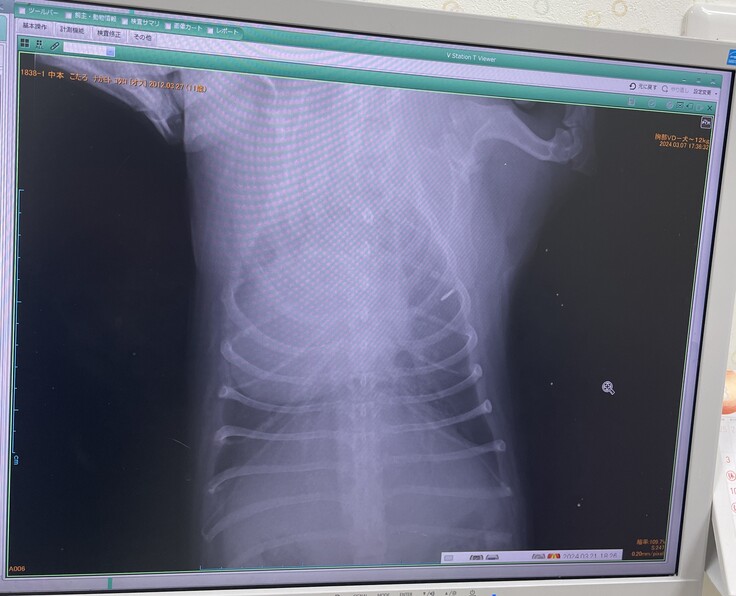

▼レントゲン

去年2月より心臓が大きくなっており肺・呼吸器が圧迫されていて咳が出る状態

(普通のわんこは真ん中に心臓があるが、こたろは左に寄っていて、

これが生まれつきなのかはわからないとの事)

※掲載画像はすべて病院からの許可をいただいています